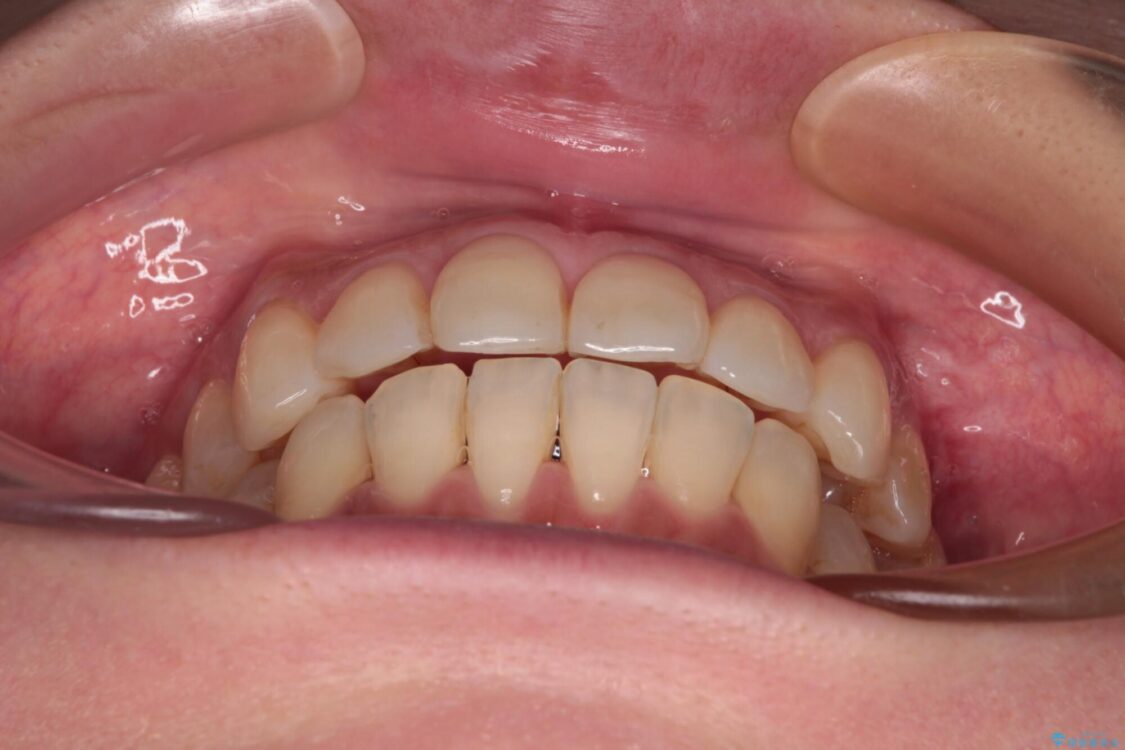

治療途中

• インビザラインによる矯正治療と奥歯のインプラント治療 治療途中画像